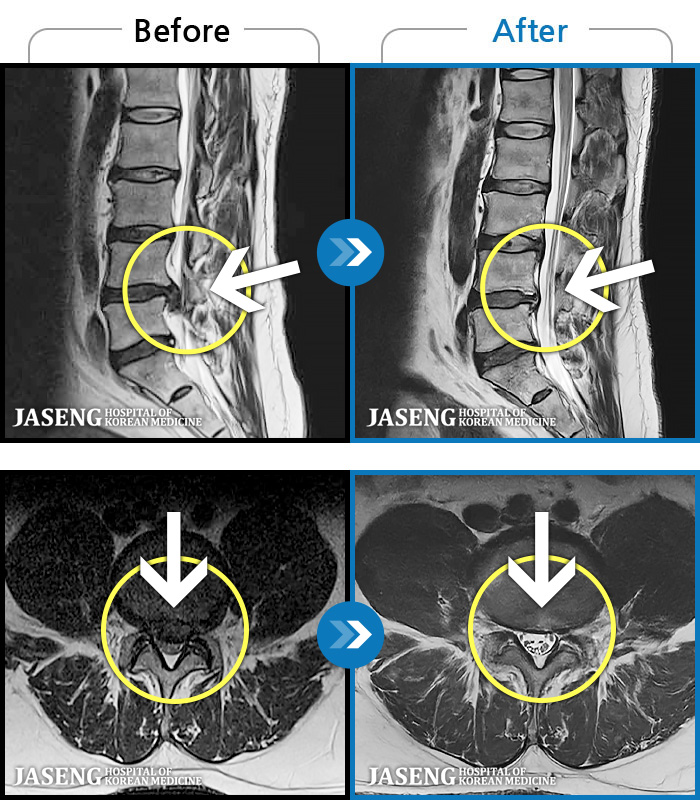

MRI ġ

1,240 MRI ũ ʸ Ȯϼ.

[_㸮ũ] 㸮 ϰ , ̾ ϼ̽ϴ.

[ϻ_㸮ũ] ϰ ӵǾϴ. ߰ Ͽ ߰ Ǵ ߵ ̻ ȣϴ ¿ϴ.

[λ_㸮ũ] 㸮 㸮 ̸ ִ.

[Ȼ_㸮ũ] 㸮 ְ ٸ ȱⰡ .

[_㸮ũ] 㸮 , ٸ ̾ ϼ̽ϴ.

[õ_㸮ũ] ߲ 㸮 , ٷ

[ϻ_㸮ũ] ݺ ӵǸ ڼ ÿ ȭǴ ߵ ̻ ȣϴ ¿ϴ.

[ϻ_㸮ũ] ؽϰ ߰ ̴ · ϻȰ ¿ϴ.

[ؿ_㸮ũ] 㸮 ϰ